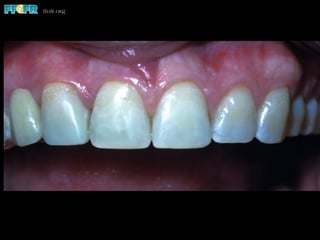

Tooth Discoloration

•  Increases with time

4% after 7 years

25% after 10 years

37% after 15 years

Thayer, 1993

The lingual metal produces discoloration, particularly

through translucent portions of the abutment teeth